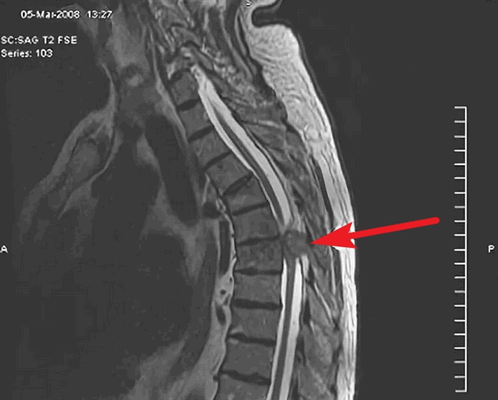

Наиболее безопасным и эффективным способом, позволяющим диагностировать опухоль спинного мозга, выступает МРТ позвоночника. Метод дает возможность послойно визуализировать расположенные в позвоночном столбе мягкотканные образования, проанализировать объем и распространенность опухоли, ее локализацию по отношению к веществу, оболочкам и корешкам спинного мозга, сделать предварительную оценку гистоструктуры новообразования.

- Томография. Наиболее достоверным методом, визуализирующим экстрамедуллярные опухоли является МРТ позвоночника. Она дает возможность определить точное расположение, распространенность, форму опухоли, предположить ее вид, оценить степень спинальной компрессии. При наличии противопоказаний к МРТ альтернативным методом выступает КТ-миелография.

3. Магнитно-резонансная томография (МРТ) с контрастным усилением. На данный момент это основной метод диагностики новообразований спинного мозга. МРТ позволяет визуализировать весь спинной мозг и позвоночник и определить локализацию опухоли. Накопление контрастного вещества определяет не только распространение, но и гистологическую структуру опухоли [5] [6] .